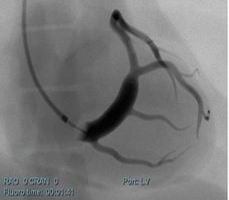

冠狀動脈介入手術(shù)模塊

可練習(xí)冠狀動脈支架手術(shù)的完整過程:造影診斷、導(dǎo)絲通過、導(dǎo)引導(dǎo)管的放置、預(yù)擴張、自擴張支架放置、后擴張、以及再造影等